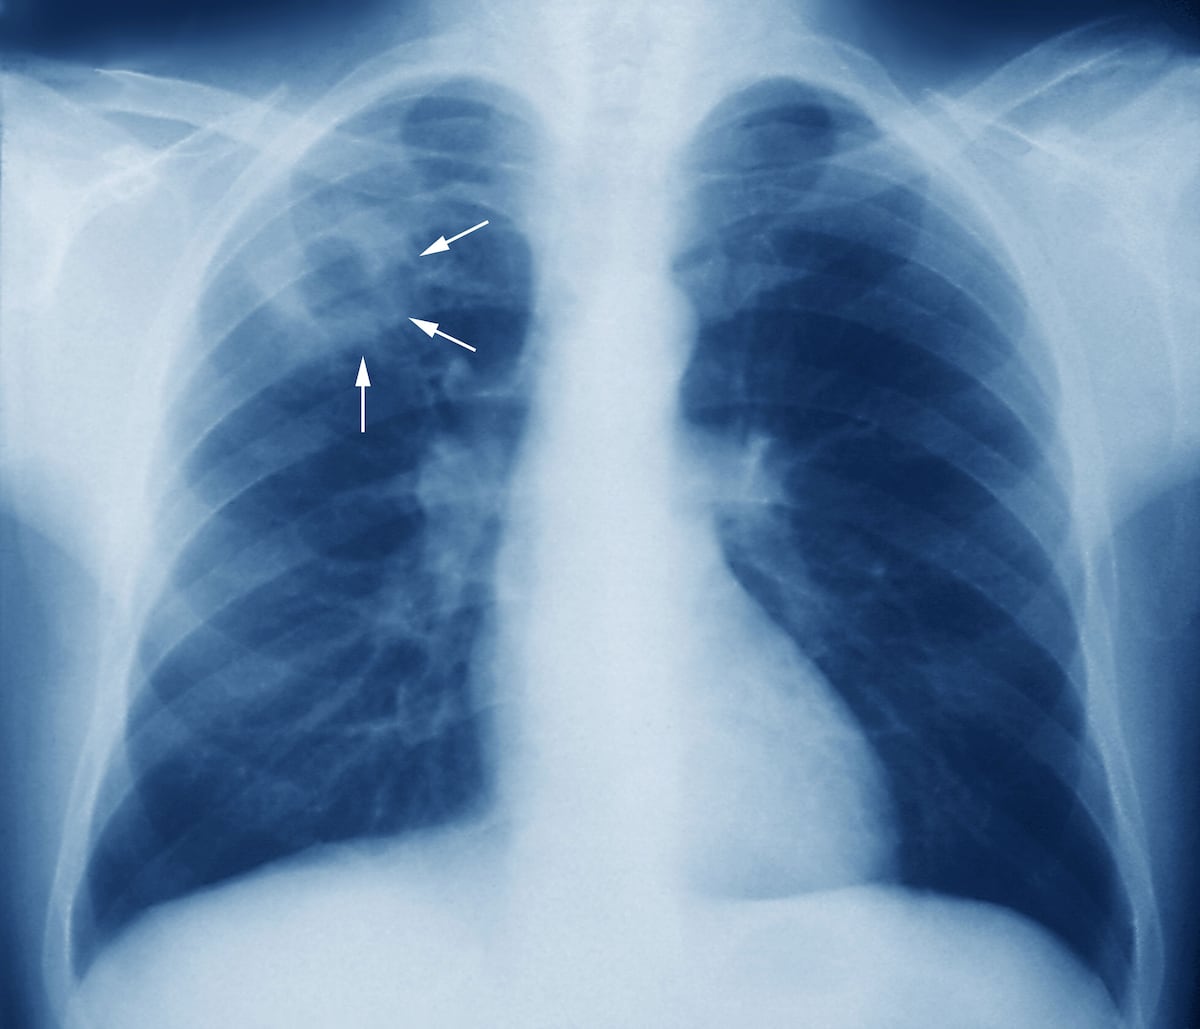

La tuberculosis es una enfermedad infecciosa que suele afectar los pulmones, causada por la bacteria Mycobacterium tuberculosis. Se transmite de una persona a otra a través de gotitas de aerosol suspendidas en el aire, que son expulsadas por personas con la enfermedad pulmonar activa, explicó Carlos Gartner, coordinador nacional del Programa de Tuberculosis de la Caja de Seguro Social (CSS).

Por lo tanto, Gartner resaltó la importancia de que se realice un diagnóstico temprano. ”Cuando se tiene un cuadro de tos por más de 15 días, pudiéramos encontrar la tuberculosis cuando aún no ha hecho daño a los pulmones, la podemos tratar y evitar complicaciones”, señaló.

Pero la realidad –añadió– es que todavía se hacen muchos diagnósticos en el hospital cuando el paciente llega con complicaciones. “Un paciente que ya tiene sudoración nocturna, pérdida de peso, fiebre vespertina, posteriormente tos con sangre, en ese momento ya hay una lesión en los pulmones y ese paciente está expectorando muchos bacilos que pueden ser inhalados por cualquier otra persona sana”, subrayó.

Gartner insistió en que si se diagnostica la enfermedad en sus fases iniciales, se evitarán lesiones graves en los pulmones que luego son “irreversibles”. En ese sentido, recalcó que la tuberculosis es tratable, curable y prevenible.